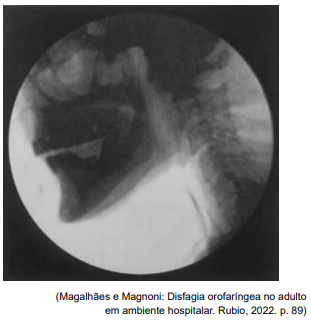

Segundo Magalhães e Magnoni (2022), nos pacientes

oncológicos, principalmente com câncer de cabeça e

pescoço, há modificações na anatomia e é importante

conhecê-las para melhor avaliação.

Observe o exame a seguir:

O resultado do exame apresentado é compatível com um exemplo de

Observe o exame a seguir:

O resultado do exame apresentado é compatível com um exemplo de